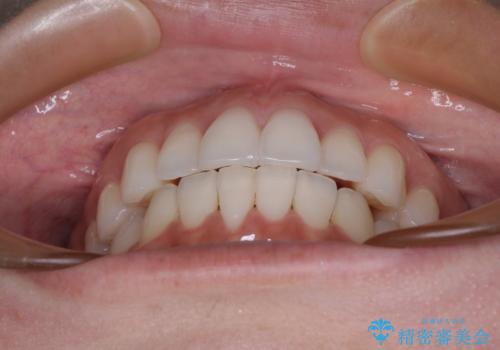

前歯のクロスバイト インビザラインによる矯正治療

- 上下のクロスバイトと前歯のデコボコを気にして来院された患者様です。

インビザラインを用い、IPR(歯と歯の間を削る)と歯列全体を拡大させることで、歯並びを整えていくこととしました。

治療を急いでいらっしゃらなかったため、のんびりと治療を進めていきました。3年以上の期間を要しましたが、きれいな口元に仕上がりました。